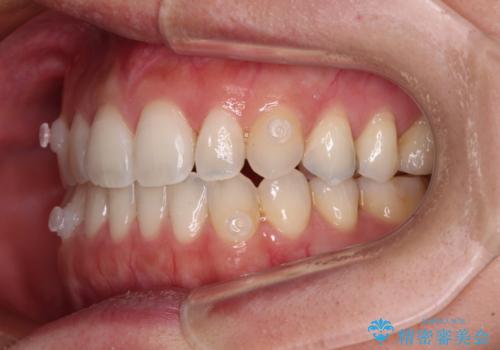

【モニター】狭い上顎歯列とオープンバイト 急速拡大装置を用いた矯正治療

- インビザライン

- 前歯の開咬を気にして来院された患者様です。

上顎歯列が狭窄していたため、急速拡大装置により上顎骨を側方に拡大し、その後インビザラインにて矯正治療を行うこととしました。

舌の突出癖が開咬の原因であったので、改善のための舌トレーニングを行っていただきました。

舌トレーニングは後戻りにも大きく影響するため、とても重要なトレーニングです。